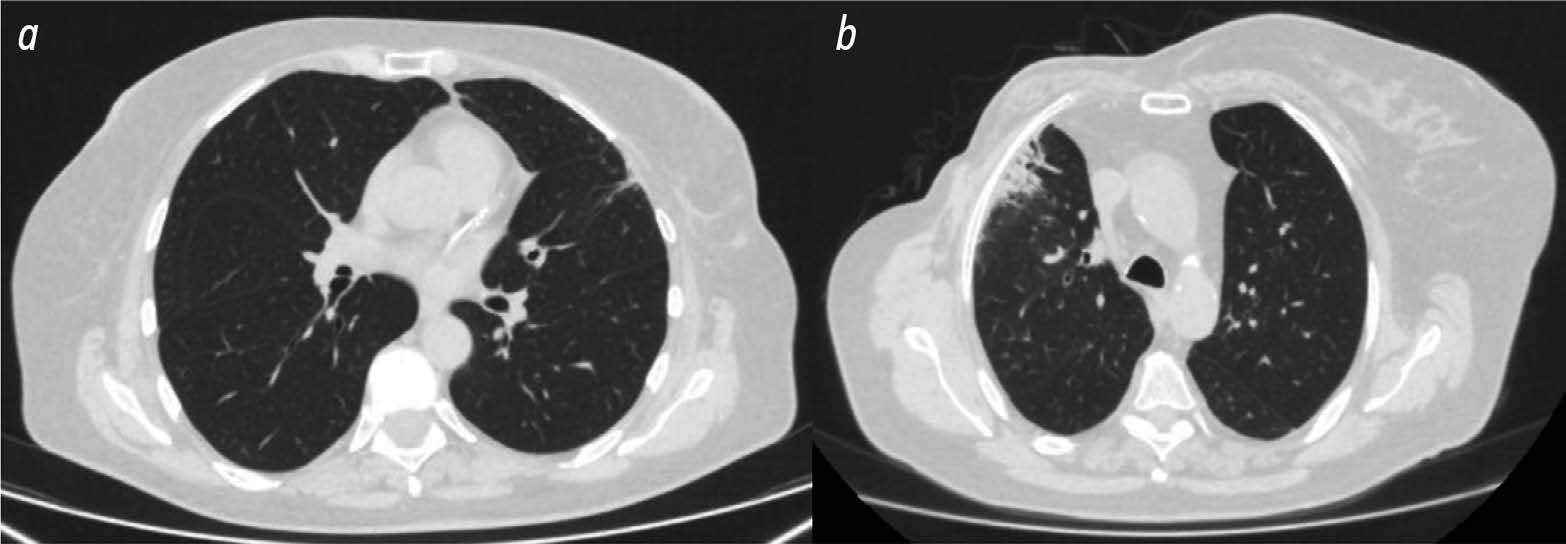

BACKGROUND: Radiomics is a machine learning based technology that extracts, analyzes, and interprets quantitative features from digital medical images. In recent years, dosiomics has become an increasingly common term in the literature to describe a new radiomics method. Dosiomics is a texture analysis method for evaluating radiotherapy dose distribution patterns. Most of the published research in dosiomics evaluates its use in predicting radiation induced lung injury.

AIM: The aim of the study was to identify predictors (biomarkers) of radiation induced lung injury using texture analysis of computed tomography (CT) images of lungs and chest soft tissues using radiomics and dosiomics.

MATERIALS AND METHODS: The study used data from 36 women with breast cancer who received postoperative conformal radiation therapy. Retrospectively, the patients were divided into two groups according to the severity of post radiation lung lesions. 3D Slicer was used to evaluate CT results of all patients obtained during radiation treatment planning and radiation dose distribution patterns. The software was able to unload radiomic and dosiomic features from regions of interest. The regions of interest included chest soft tissue and lung areas on the irradiated side where the dose burden exceeded 3 and 10 Gy.

RESULTS: The first group included 13 patients with minimal radiation induced lung lesions, and the second group included 23 patients with post radiation pneumofibrosis. In the lung area on the side irradiated with more than 3 Gy, statistically significant differences between the patient groups were obtained for three radiomic features and one dosiomic feature. In the lung area on the side irradiated with more than 10 Gy, statistically significant differences were obtained for 12 radiomic features and 1 dosiomic feature. In the area of chest soft tissues on the irradiated side, significant differences were obtained for 18 radiomic features and 4 dosiomic features.

CONCLUSIONS: As a result, a number of radiomic and dosiomic features were identified which were statistically different in patients with minimal lesions and pulmonary pneumofibrosis following radiation therapy for breast cancer. Based on texture analysis, predictors (biomarkers) were identified to predict post radiation lung injury and identify higher risk patients.